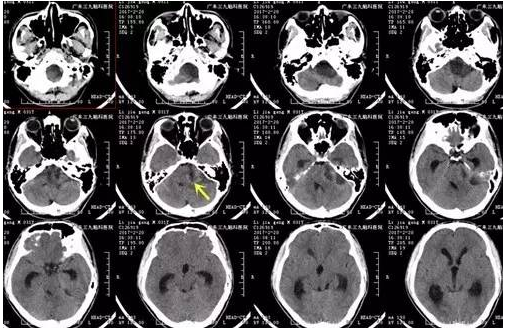

李某某,男,31岁,左侧面部麻木、耳鸣、听力下降2月,门诊CT显示颅内占位病变,遂安排入院治疗。入院后完善相关术前检查,磁共振显示左侧桥小脑角区5.2CM*2.8CM*5.6CM囊实性异常信号影,囊变的肿瘤已经将脑干压得很薄,手术中轻微牵拉囊壁就会导致心跳减慢或停止,为保证病人的安全性以及手术成功,科室组织专家反复对手术的过程进行研讨,最后决定择期行全麻下左侧桥小脑角占位性病变切除术,手术由广东三九脑科医院神经外一科主任张良主刀完成,术中见肿瘤包膜完整,分为囊实性两部分,术后过程顺利,术后患者恢复良好,未见并发症,术后MR提示肿瘤切除。

↑术前CT